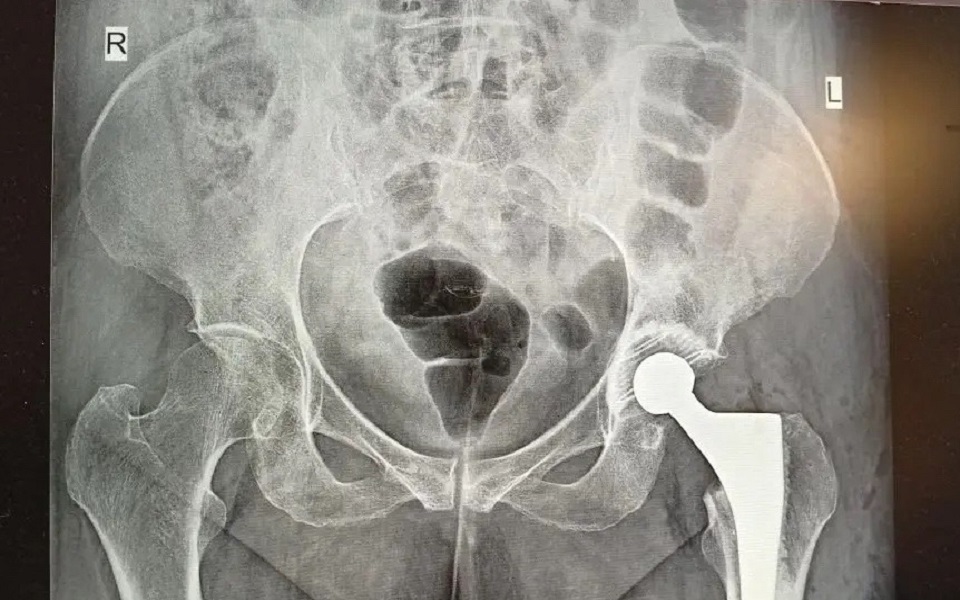

Пожилой пациентке провели эндопротезирование.

95-летняя рязанка попала в травматологию БСМП с переломом бедренной кости. В таком возрасте это очень опасный диагноз: часто он оборачивается инвалидностью и невозможностью встать с постели.

Врачи БСМП провели обследование и приняли решение делать эндопротезирование – заменить поврежденный тазобедренный сустав искусственным. Операцию провели в течение первых же суток после поступления пациентки в больницу.